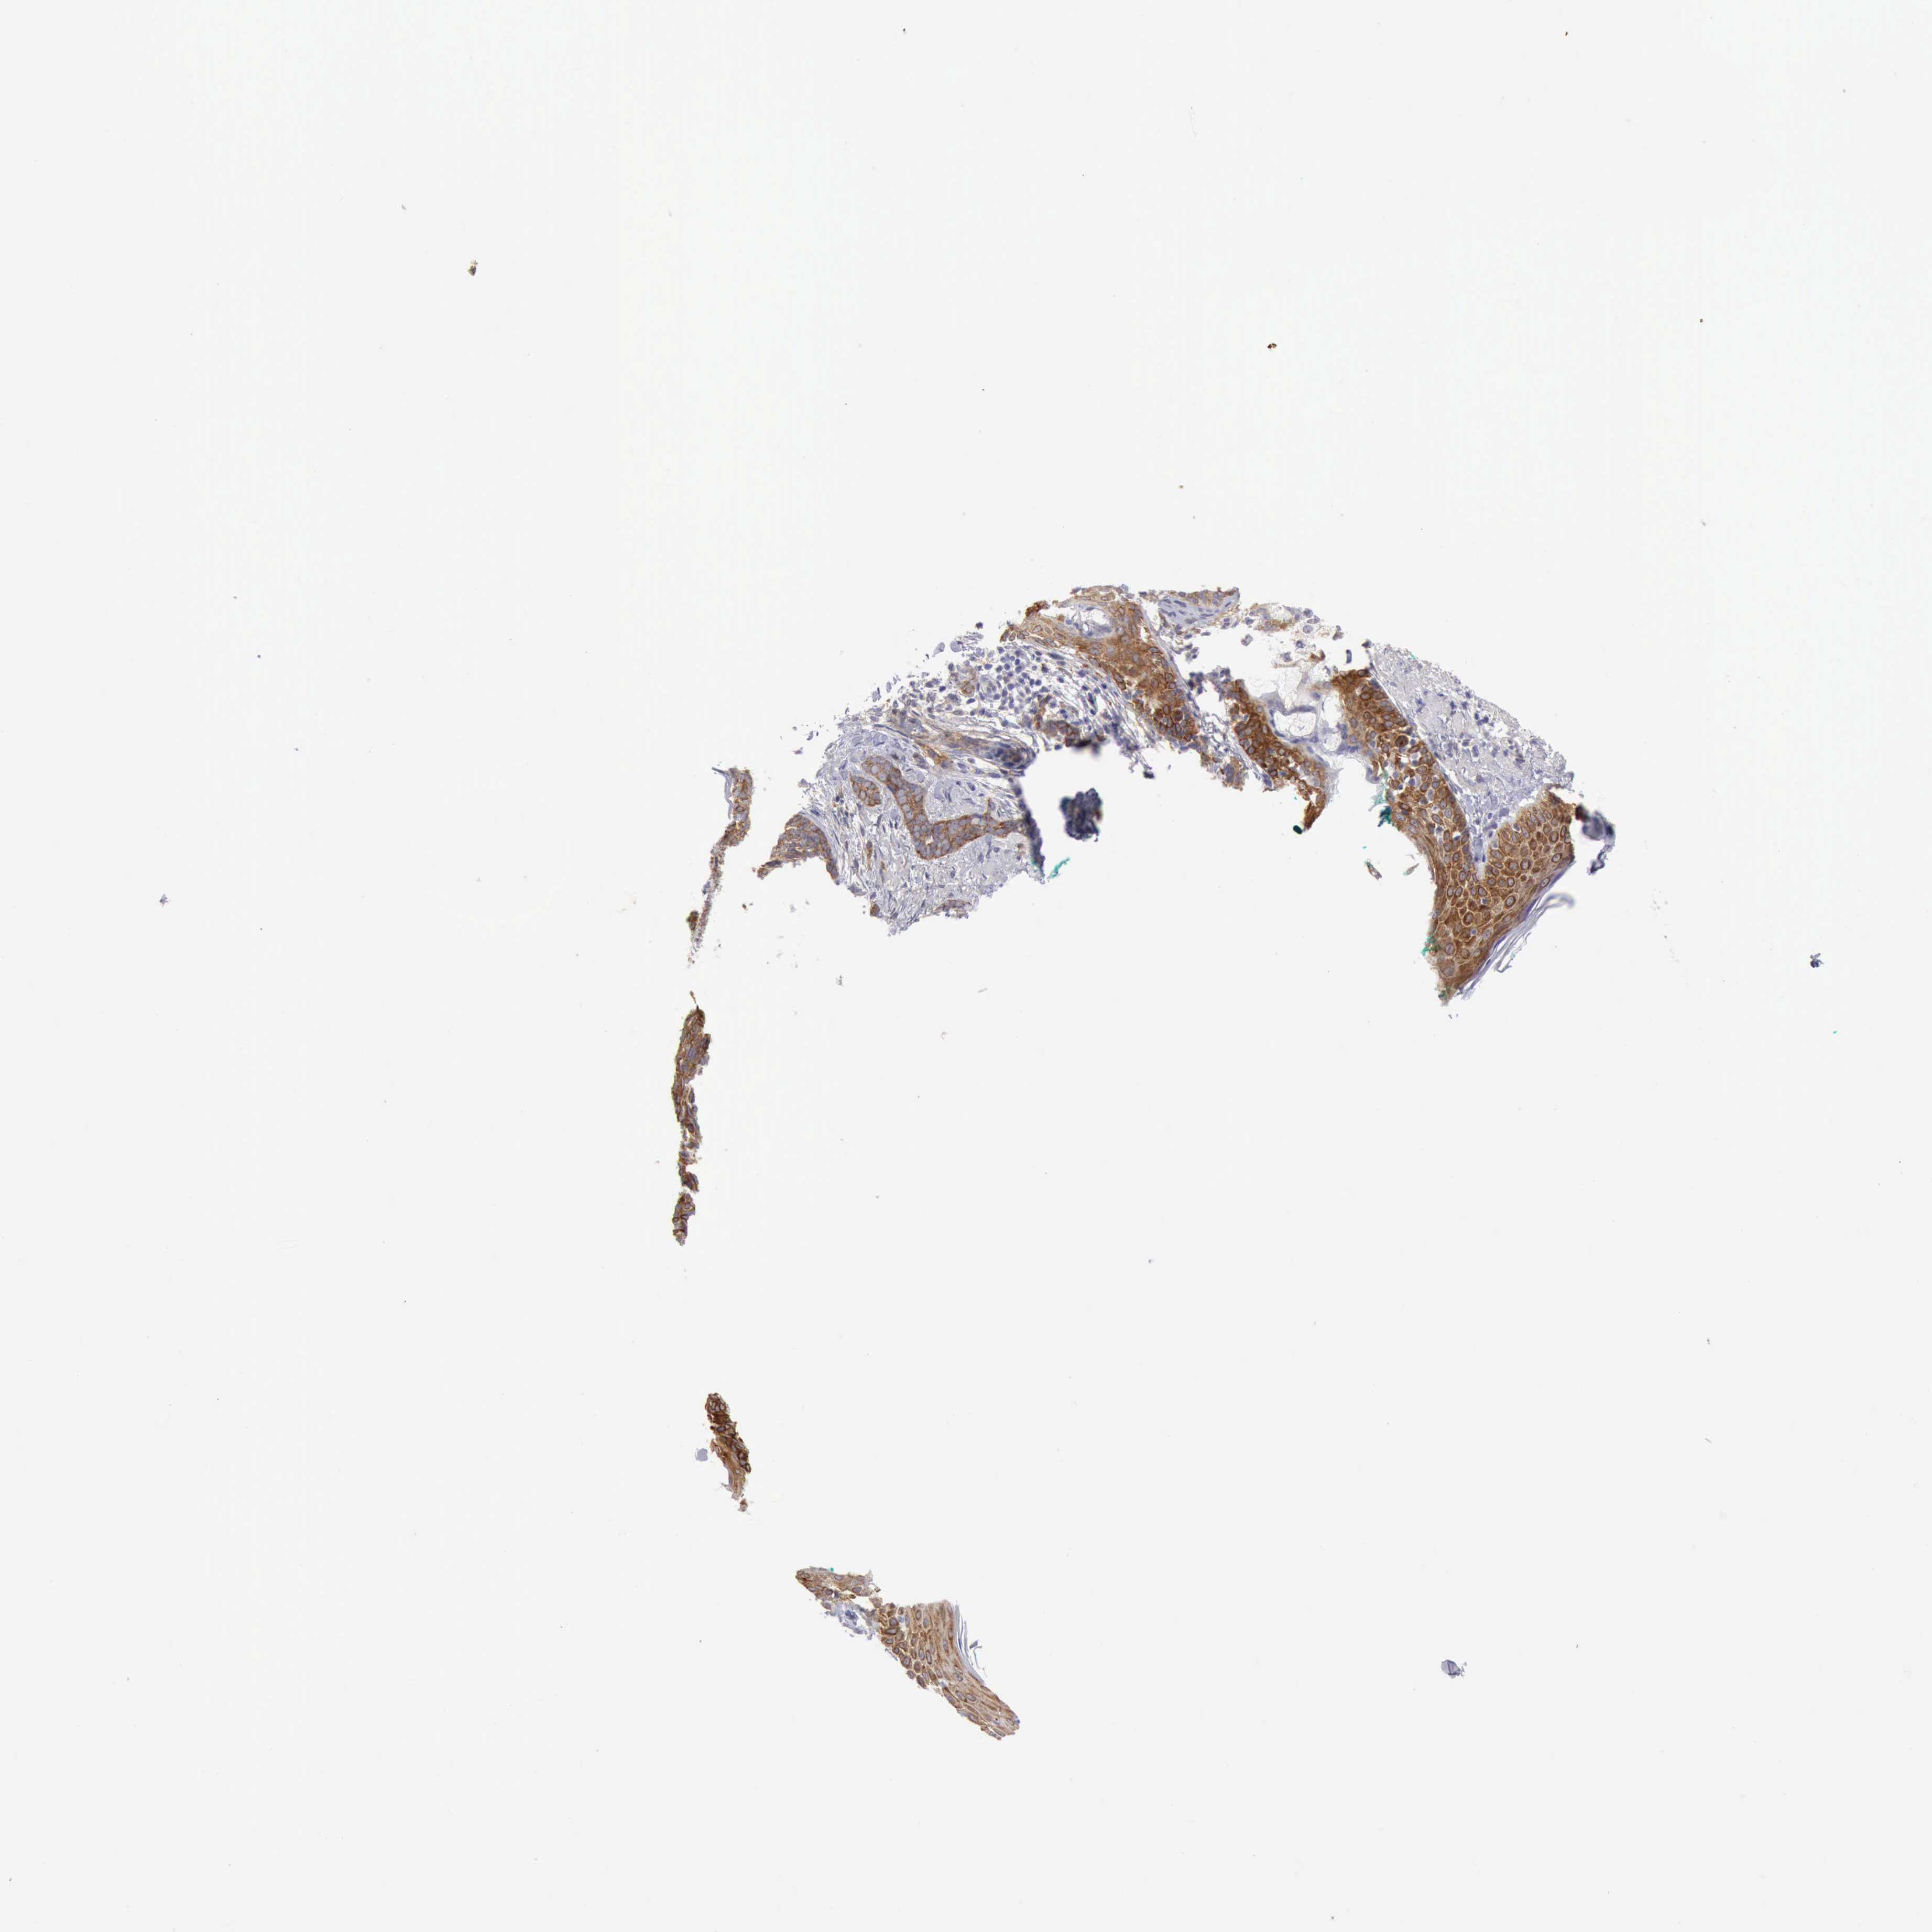

SKIN CANCER - Protein expressioni

A mouse-over function shows sample information and annotation data. Click on an image to view it in a full screen mode. Samples can be filtered based on level of antibody staining by selecting one or several of the following categories: high, medium, low and not detected. The assay and annotation is described here.

Each image is clickable and will lead to virtual microscopy that enables deeper exploration of all samples and also displays staining intensity scores, fraction scores and subcellular localization as well as patient and tissue information for each sample.

Antibody HPA028598

Basal cell carcinoma